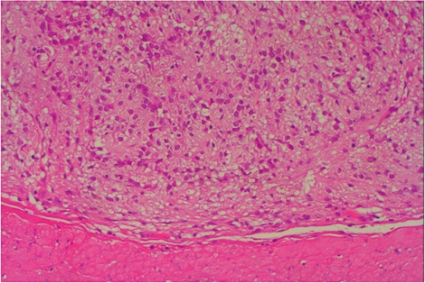

Den vanligaste submukösa tumören är gastrointestinal

stromacellstumör (GIST), som utgår ifrån muscularis propria eller muscularis mucosae (Figur 4). Vid storlek >3 cm, oregelbundna kanter och heterogen ekogenitet ökar risken för malignitet, men det kan vara svårt att skilja mellan benign och malign GIST endosonografiskt, och då kan man ta vävnadsprov med EUS-FNA eller vävnadsbiopsi för cytologisk analys av mitotiskt index. Immunhistokemisk analys hjälper inte bara till med diagnostiken av GIST, utan underlättar också differentialdiagnostiken mot andra ovanligare tumörer såsom leiomyom, leiomyosarkom och schwannom. En diagnostisk markör för GIST är c-Kit (CD117), medan desmin och S-100-protein är vanligare uttryckt i leiomyom, leiomyosarkom och schwannom.